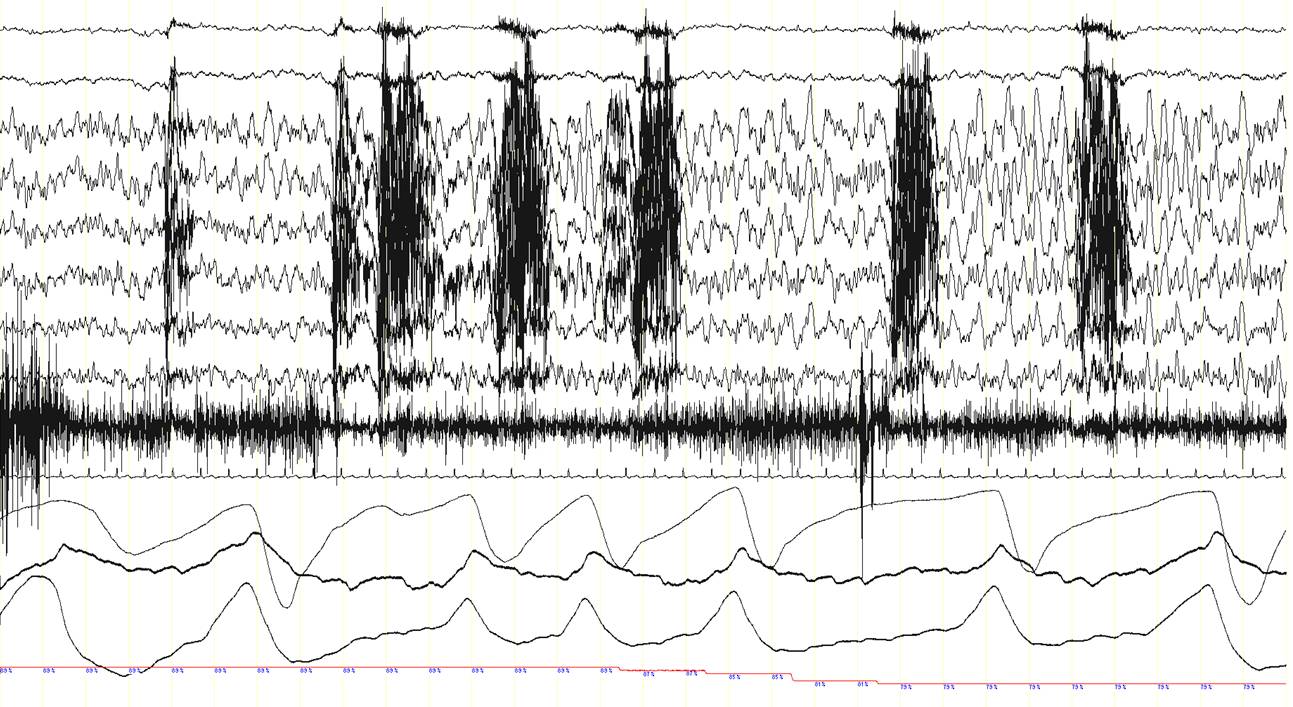

A 63 year-old man was diagnosed with obstructive sleep apnea syndrome because of habitual heavy snoring with breathing pauses during sleep, occasional awakenings and mild excessive daytime somnolence. The patient also complained of recurrent episodes of sudden dizziness, pallor, sweating, and sometimes pain in the right shoulder, either awake or during sleep. An electroencephalography (EEG), brain CT scan and cardiac exercise stress test revealed normal findings and the nature of these episodes had remained elusive. A baseline polysomnographic (PSG) study showed frequent obstructive sleep apneas, particularly in the supine position (apnea-hypopnea index in this position: 33/hour; not shown here). A subsequent continuous positive airway pressure (CPAP) titration PSG study was performed. With a CPAP pressure of 7 cm H2O obstructive events were well-controlled. Suddenly, however, the patient presented an apnea (panel A, between arrows) with a change in the EEG signals. This is shown in the three consecutive 30-second epochs (panel A, B and C). In panel D, a 20-second epoch of the event is shown. Can you describe what is happening here?

Note the presence of epileptogenic activity on the EEG channels just after the onset of the central apnea while the patient is in NREM sleep (N2). A rhythmic 8-9 Hz EEG activity is recorded in the left frontal area (red arrow, F3-REF), which rapidly spreads over the rest of the hemisphere and to the contralateral side (green arrow), and progressively increases in amplitude and decreases in frequency to theta (4-5 Hz) and finally delta ranges (2-3 Hz) (blue arrows). This ictal EEG rhythmic activity lasted approximately 1 minute (end of the ictal rhythm: red arrow in the third epoch; panel C). Remarkably, during this seizure with an initial ictal central apnea, oxyhemoglobin saturation dropped to 73%. The patient also presented repetitive chewing movements (see the artefact caused by masticatory movements in the EEG channels; red asterisks), but overt convulsions or other abnormal movements or behaviours were not recorded. The patient was unaware of this seizure and did not recall any event during the night the following morning.